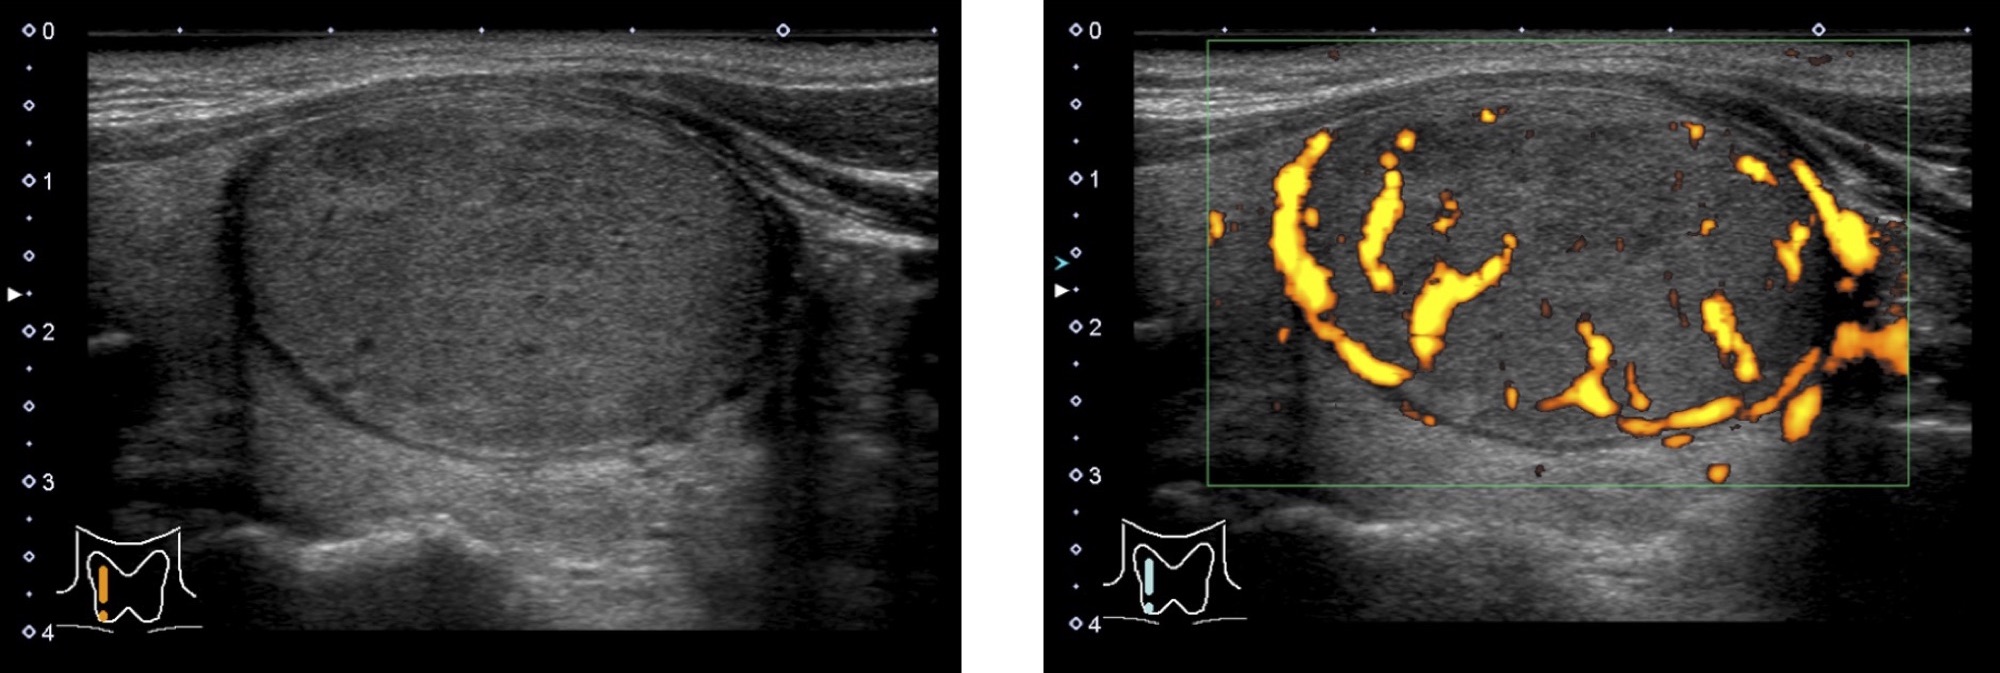

濾胞腺腫

形は円形から楕円形で、甲状腺との境界がはっきりしていることが多いです(境界明瞭)。

内部は充実性(固体)のことが多いです。

悪性腫瘍の濾胞がんとは区別が難しい場合が多いです。